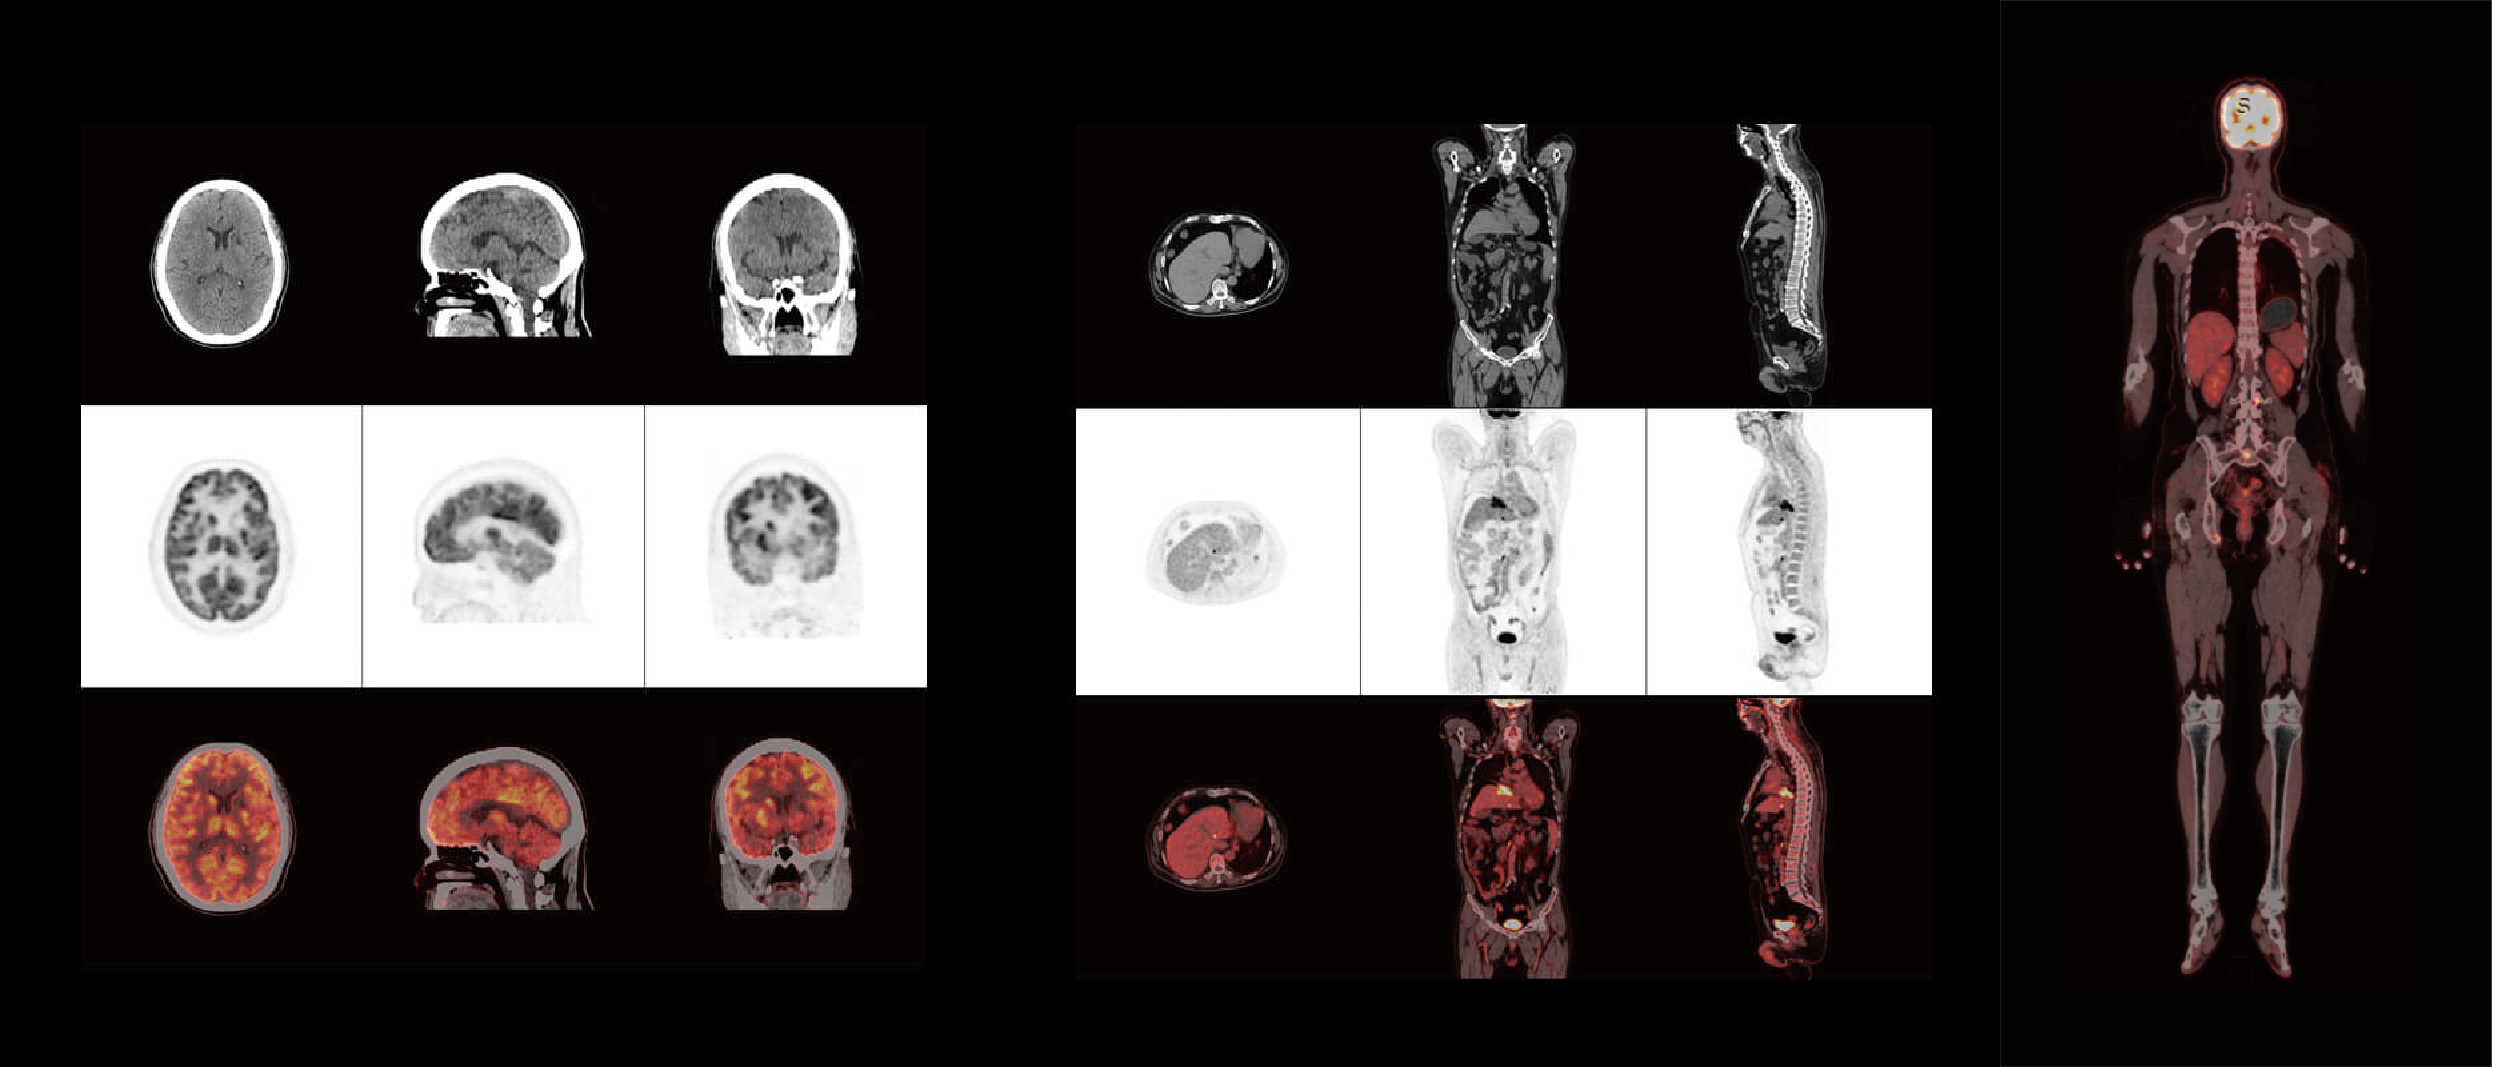

臨床畫廊